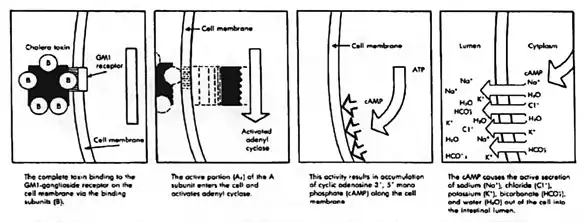

During infection, V. cholerae secretes cholera toxin (CT), a protein that causes profuse, watery diarrhea (known as "rice-water stool").[33][5] This cholera toxin contains 5 B subunits that plays a role in attaching to the intestinal epithelial cells and 1 A subunit that plays a role in toxin activity. Colonization of the small intestine also requires the toxin coregulated pilus (TCP), a thin, flexible, filamentous appendage on the surface of bacterial cells. Expression of both CT and TCP is mediated by two component systems (TCS), which typically consist of a membrane-bound histidine kinase and an intracellular response element.[34] TCS enable bacteria to respond to changing environments.[34] In V. cholerae several TCS have been identified to be important in colonization, biofilm production and virulence.[34] Quorum regulatory small RNAs (Qrr RNA) have been identified as targets of V. cholerae TCS.[34][35][36] Here, the small RNA (sRNA) molecules bind to mRNA to block translation or induce degradation of inhibitors of expression of virulence or colonization genes.[34][35] In V. cholerae the TCS EnvZ/OmpR alters gene expression via the sRNA coaR in response to changes in osmolarity and pH. An important target of coaR is tcpI, which negatively regulates expression of the major subunit of the TCP encoding gene (tcpA). When tcpI is bound by coaR it is no longer able to repress expression tcpA, leading to an increased colonization ability.[34] Expression of coaR is upregulated by EnvZ/OmpR at a pH of 6,5, which is the normal pH of the intestinal lumen, but is low at higher pH values.[34] V. cholerae in the intestinal lumen utilizes the TCP to attach to the intestinal mucosa, not invading the mucosa.[34] After doing so it secretes cholerae toxin causing its symptoms. This then increases cyclic AMP or cAMP by binding (cholerae toxin) to adenylyl cyclase activating the GS pathway which leads to efflux of water and sodium into the intestinal lumen causing watery stools or rice watery stools.